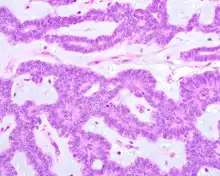

Canalicular adenoma growths are usually small at the time they are noticed, with an average size of about 1.6 cm.[1] Their histologic appearance is very distinct, with a channel-like pattern between cords and ribbons; the pattern has been described as resembling a "string of pearls."

The growths often contain are often small bight squamous balls, or morules. They also tyipcally contain a well-developed supporting tissue - a fibrous stroma - which is rich in hyaluronic acid and chondroitin sulphate.[1] In a few cases, the growths may contain small calcium deposits or microliths. Although it is seldom necessary, a pathologist can confirm the existence of canalicular adenoma through immunohistochemistry studies, with the cells reacting with pancytokeratin, S100 protein and SOX10, with a delicate GFAP reaction around the periphery.[5][1][6][7] Although it is a benign tumor, a positive diagnosis of canalicular adenoma may be necessary to exclude the existence of other medical conditions such as a basal cell adenoma, pleomorphic adenoma, adenoid cystic carcinoma, and polymorphous adenocarcinoma.